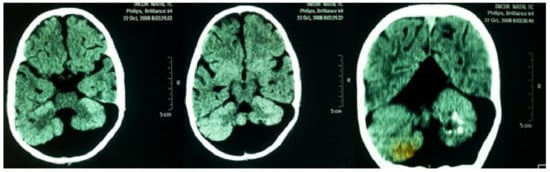

A neurological examination showed global hypotonia, decreased strength, bilaterally exaggerated deep tendon reflexes and significant delay in neuropsychomotor development (NPMD). Around the age of two years, sporadic tonic-generalized seizures began and phenobarbital was prescribed since then. An electroencephalogram detected focal discharges. Computed tomography, without contrast of the head, showed the following findings: massive cystic formation in the posterior fossa inferiorly compressing the occipital parenchyma; hypoplasia of cerebellar vermis with calcifications in the left cerebellar hemisphere; moderate dilation of the IV ventricle; dilatation of the supratentorial ventricular system; elevated sinus and Torcular of Herophilus (Figure 5). These findings are compatible with DWS. Currently, the patient is being regularly followed by a pediatrics team in the regional university hospital.

Figure 5. Computed tomography, without contrast of the head, showing massive cystic formation in the posterior fossa inferiorly compressing the occipital parenchyma; hypoplasia of cerebellar vermis with calcifications in the left cerebellar hemisphere. Findings compatible with Dandy-Walker syndrome.